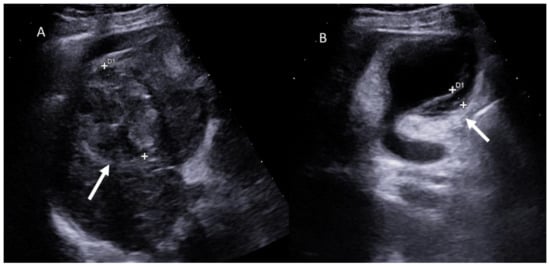

- Battaglia, V.; Cervelli, R. Liver investigations: Updating on US technique and contrast-enhanced ultrasound (CEUS). Eur. J. Radiol. 2017, 96, 65–73. [Google Scholar] [CrossRef]

- Faccia, M.; Garcovich, M.; Ainora, M.E.; Riccardi, L.; Pompili, M.; Gasbarrini, A.; Zocco, M.A. Contrast-Enhanced Ultrasound for Monitoring Treatment Response in Different Stages of Hepatocellular Carcinoma. Cancers 2022, 14, 481. [Google Scholar] [CrossRef]